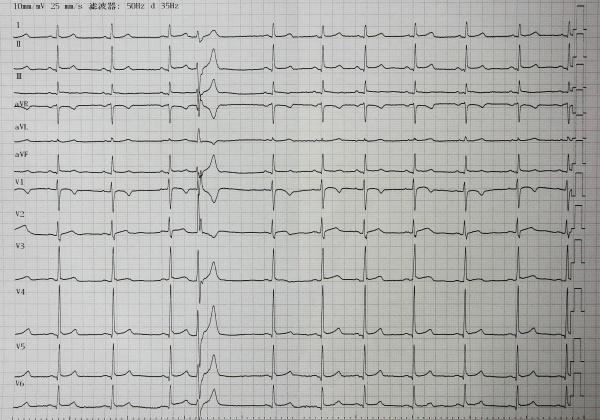

请各位老师分析下是否存在 二度Ⅰ型窦房阻滞?女,37岁,胸闷,过往心电图正常

窦房结内游走性心律与窦房结心房游走心律本身就是很难鉴别的,个人习惯采取窦性p波转为倒置P波且P'R间期大于0.12秒的,考虑窦房结心房游走性心律,像本图长导联p波直立,只是振幅的变化,我常考虑窦房结内游走心律。仅供参考

支持窦房结心房游走心律,室性早搏

支持nikkive版主,没有窦房阻滞。P-P间期不规律,P-R间期、P波形态不完全一致。考虑窦房结心房游走心律,室性早搏。仅供参考,请老师指导。